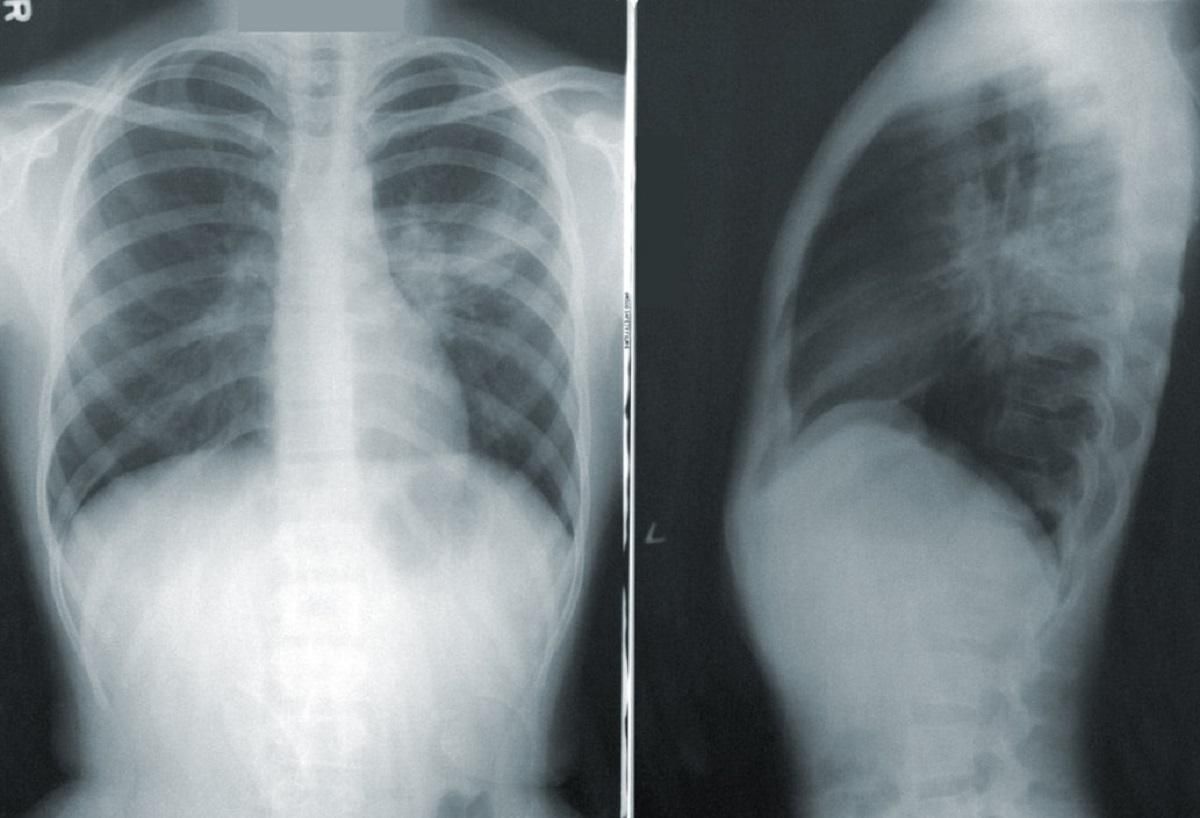

Від сьогодні ми тестуємо всі пневмонії, які перебувають в інфекційних лікарнях, а також лікарнях іншого профілю,

Зазначимо, що деякі регіони почали й раніше тестувати усіх пацієнтів з діагнозом пневмонія, зокрема Київ.